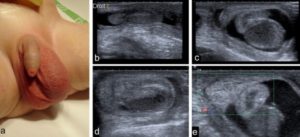

Со временем киста (фото есть в данной статье) начинает разрастаться. Когда опухоль достигает 2-х сантиметров, мужчина начинает ощущать давление на мошонку. Может появиться деформация яичка. Появляются терпимые тянущие боли в области живота. Иногда наблюдается его вздутие, ощущается давление. Во время секса появляются сильные боли.

Чаще всего новообразование полостное или целостное, гладкое, мягкое, при аппаратном исследовании видны четкие контуры, гипоэхогенность говорит о заполнении жидкостью. Вместе с этим могут выявляться дистрофические или метаболические изменения.

Фото кисты яичка у мужчин

- ультразвуковое исследование мошонки;

- диафаноскопия – оценка проходимости ультрафиолета через орган, в случае обнаружения кисты с жидкостью, она подсвечивается розовым.